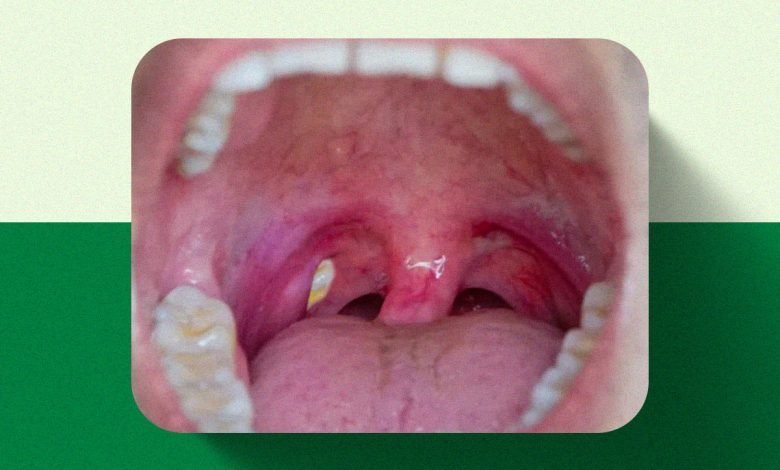

As chamadas bolinhas brancas na garganta costumam assustar à primeira vista, mas, na maioria dos casos, não representam uma doença grave. Elas aparecem, sobretudo, nas amígdalas e são formadas pelo acúmulo de restos de alimentos, células mortas da mucosa e bactérias. Esse material se aloja em pequenas cavidades naturais da região — conhecidas como criptas — e recebe o nome de caseum, também chamado de tonsilólito.

Do ponto de vista médico, trata-se de um fenômeno relativamente comum, especialmente em pessoas que apresentam amígdalas maiores ou mais “furadinhas”, o que favorece a retenção desses resíduos.

Embora muitas pessoas percebam apenas os pontos esbranquiçados, o caseum costuma vir acompanhado de sinais bastante característicos. O mais frequente é o mau hálito persistente, resultado da ação bacteriana sobre o material acumulado. Também podem surgir sensação de corpo estranho na garganta, gosto desagradável na boca, tosse seca frequente e leve desconforto ao engolir.

Em geral, esses sintomas são localizados e não afetam o estado geral da pessoa. Não é comum haver febre ou dor intensa, o que ajuda a diferenciar o caseum de infecções mais sérias. Ainda assim, a recorrência pode causar incômodo significativo e impactar a qualidade de vida.

A distinção entre caseum e amigdalite é essencial para evitar tratamentos inadequados. O caseum, isoladamente, não provoca febre alta, dor intensa ou mal-estar generalizado. Já a amigdalite — que pode ser viral ou bacteriana — costuma se manifestar com dor forte ao engolir, febre, aumento dos gânglios do pescoço, vermelhidão intensa e placas esbranquiçadas mais extensas.